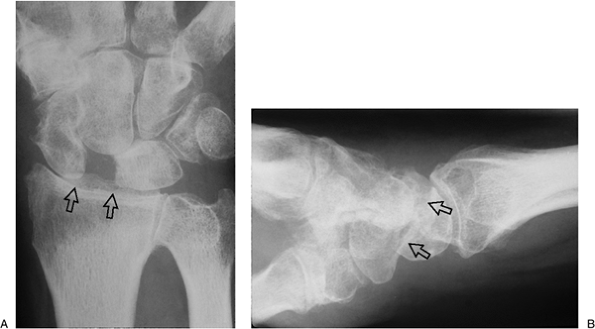

Figure 11.2-5

A lunotriquetral dissociation as shown by an arthrogram. Note the presence of radio-opaque dye in the space between the lunate and triquetrum (opposing arrows), indicating disruption of the lunotriquetral ligament. |

Contrast material injected into the

midcarpal joint should not extend into the radiocarpal joint unless

there is a ligament disruption in the proximal row (see Figure 11.2-5).